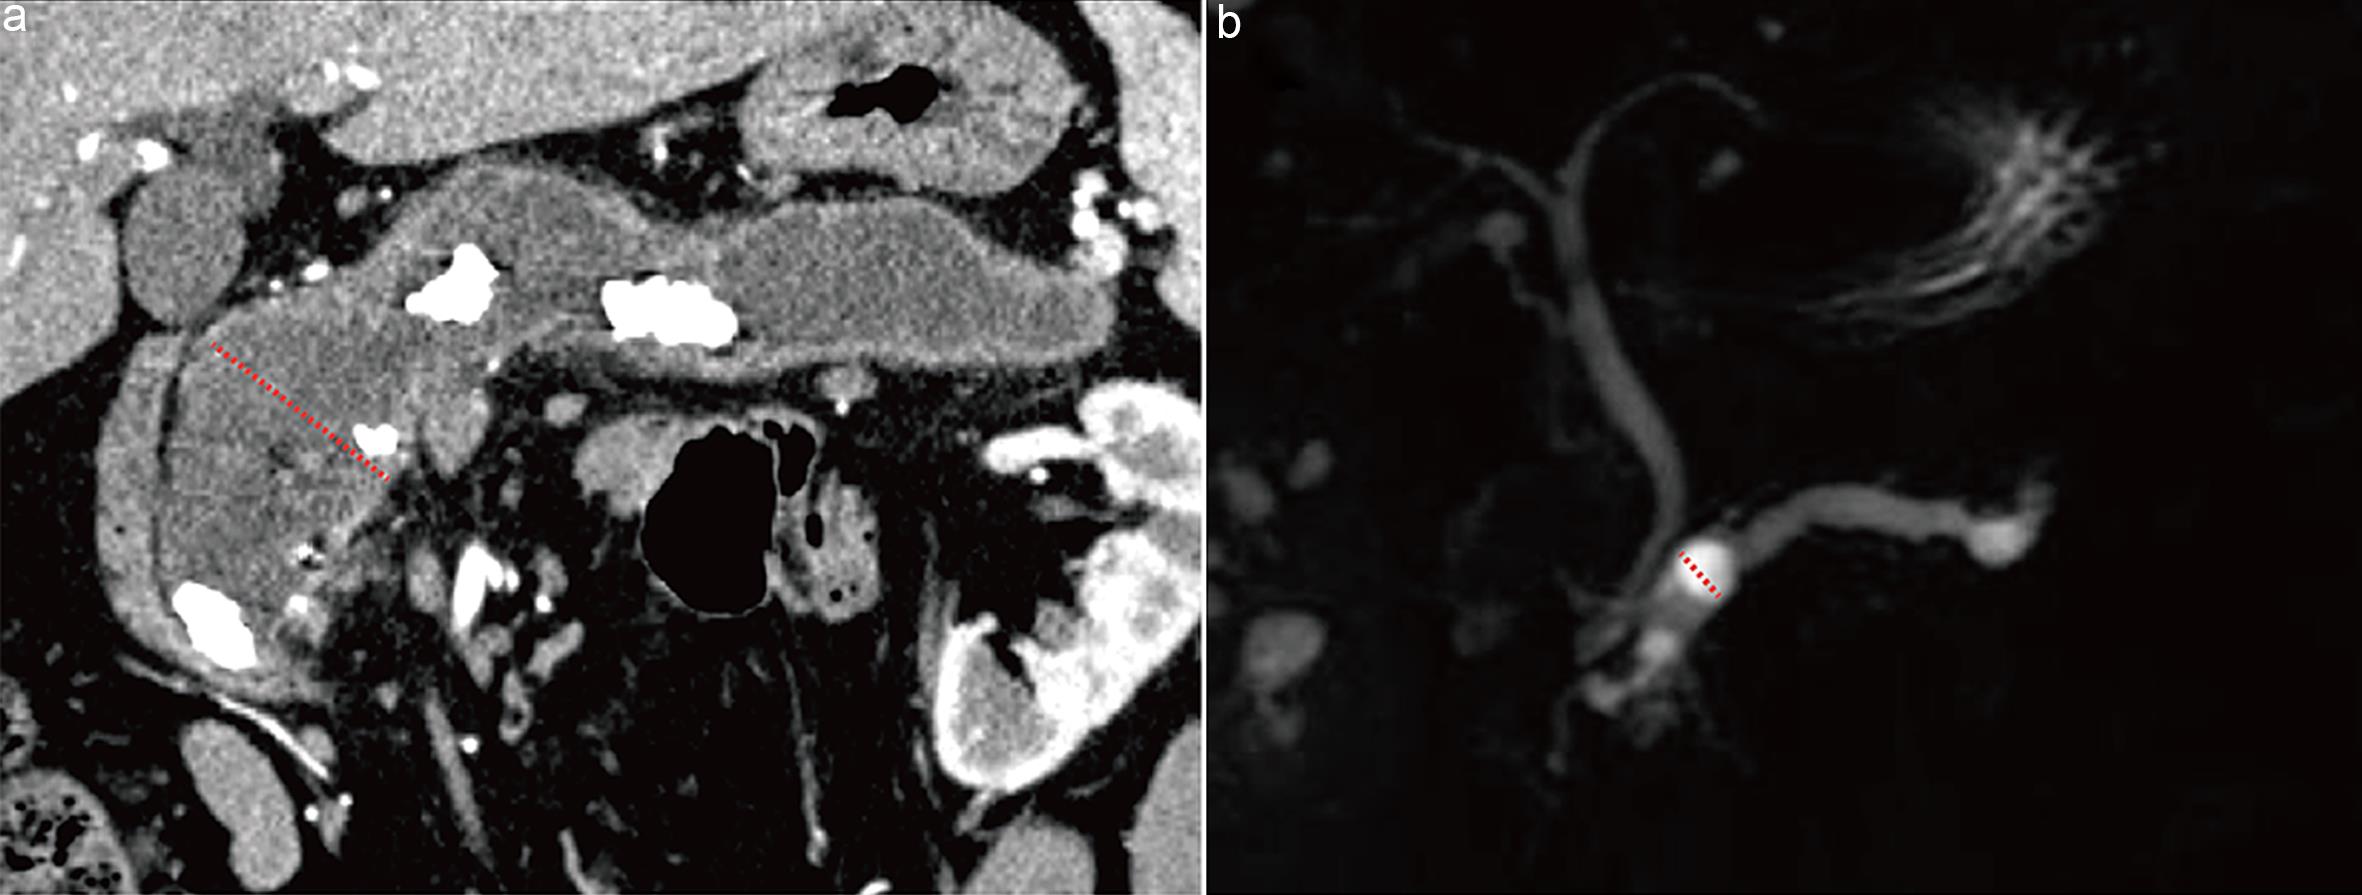

Wall nodules are defined as papillary projections ≥3 mm on the main pancreatic duct wall or cyst wall, associated with malignant tumors (carcinoma in situ or invasive carcinoma).24 For enhancing mural nodules, the pancreatic parenchymal phase of contrast-enhanced imaging provides optimal contrast between normal pancreatic parenchyma and cyst fluid, allowing clear visualization of the cyst wall structure (Fig. 3a). Non-enhancing mural nodules are difficult to visualize on post-contrast images but appear as filling defects on T2WI, where the high signal intensity of cyst fluid provides optimal contrast to delineate the nodule boundaries (Fig. 3b).17

Measurement of mural nodules.

Fig. 3  Measurement of mural nodules.

(a) Axial contrast-enhanced computed tomography (CT) image obtained during the pancreatic parenchymal phase shows an enhancing mural nodule within the main pancreatic duct in mixed-type intraductal papillary mucinous neoplasm (arrow). (b) Axial T2-weighted magnetic resonance image shows a mural nodule within the cystic lesion in a mucinous cystic neoplasm in the pancreatic tail (arrow).

Previous studies have variably defined cyst wall or septal thickening as >2 mm or >3 mm.31,32 Due to inconsistent measurement methods among radiologists, interobserver agreement is poor.33,34 Therefore, this guideline adopts the evaluation standard from renal cystic tumors35: cyst wall or septal thickness >2 mm is considered thickened (Fig. 4a).

Assessment of cyst wall/septal thickening and communication with the main pancreatic duct.

Fig. 4  Assessment of cyst wall/septal thickening and communication with the main pancreatic duct.

(a) Mucinous cystic neoplasm in the pancreatic tail. Axial portal venous phase computed tomography (CT) image shows thickened internal septations within the cyst, with septal thickness >2 mm (arrow). (b) Branch-duct intraductal papillary mucinous neoplasm in the pancreatic head. Magnetic resonance cholangiopancreatography demonstrates communication between the cystic lesion and the main pancreatic duct (arrow).

Because cyst fluid and pancreatic juice in the main duct both appear hyperintense on T2WI and MRCP, these sequences facilitate visualization of their relationship (Fig. 4b).